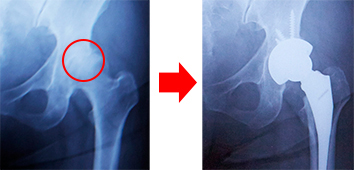

人工股関節置換術 術前と術後のX線

変形性股関節症の診断の決め手はレントゲンです。軟骨は骨と骨との間に存在しますから、レントゲン写真で見ると、骨と骨の隙間が少なくなっているのがすぐ分かります。画像で隙間の程度を確認し、本人の痛み具合などを十分に聞いてから、患者さんの年齢を考慮して治療方針を決めていきます。例えば、変形性股関節症の初期の段階であれば、筋力を鍛えるトレーニングを指導します。筋肉を付けることは、変形性股関節症の初期の段階で非常に大事です。それでも痛みが強ければ内服薬を服用します。なお、肥満の人は減量も必要です。クリニックの場合なら、温熱療法などの物理療法を行うこともあるでしょう。これらの保存療法を行いながら、筋肉の衰えを防ぐ運動を加えて、痛みが出ないような付き合い方を指導します。保存療法を3~4カ月継続しても効果があらわれない場合には、人工股関節置換術などの手術療法を選択肢として考えます。